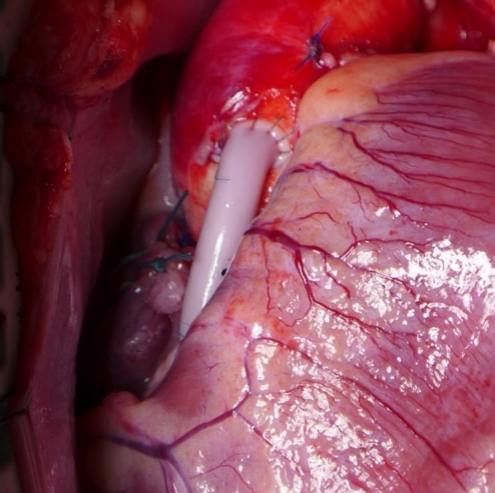

Humacyte公司2024年11月公布了3.5mm组织工程血管狒狒冠脉搭桥模型优异的临床前随访资料,计划今年开展冠脉搭桥临床试验;Medical 21公司唯一产品管线3.5mm内径人工血管,今年计划在欧洲开展冠脉搭桥确证临床试验;欧洲Xeltis公司完成冠脉搭桥FIM研究后计划今年开展冠脉搭桥临床试验。海迈医疗成立之初就布局了3.5mm内径人工血管CoroMatrix蔻迈通®用于冠脉搭桥,目前在临床前阶段,是公司最重磅的产品之一,和欧美公司研发进度一致,这款产品未来如果获批将是全球范围内冠脉搭桥“First-in-Class”人工血管产品。

Humacyte 3.5mm内径组织工程血管狒狒心脏搭桥模型 图源:参考2022年1月28日X Advanced Therapies Week-Bioengineering and the Future of Cardiac Surgery

(图片可能引起不适,请谨慎右滑)